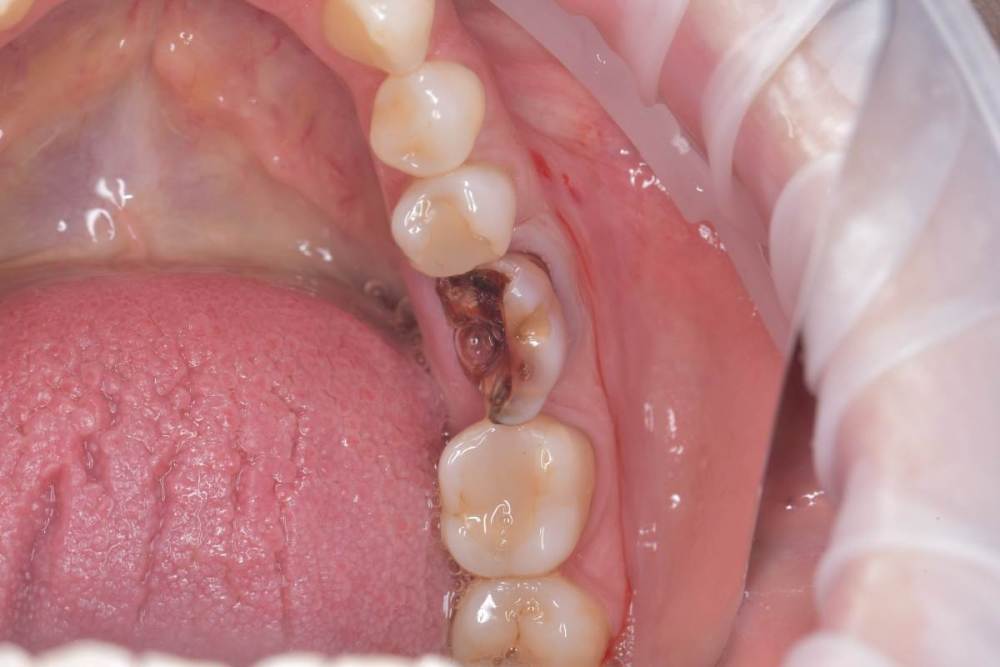

TIGER Опубликовано 22 сентября, 2022 Поделиться Опубликовано 22 сентября, 2022 Всем привет!Давно ничего не закидывал,небольшой клинический случай,банальщина,замещение одиночного моляра,система Straumann понравилась,как всегда только оригинальные компоненты? 8 1 Ссылка на комментарий